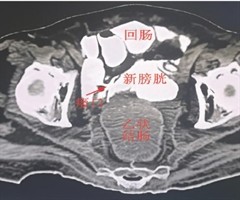

腹腔镜下改良回肠-新膀胱瘘修补术的疗效分析

Efficacy of modified laparoscopic repair of ileal-neobladder fistula HOU Yidong,ZHAO Liang,WANG Jinyou,MIN Jie,WANG Yi,Z...